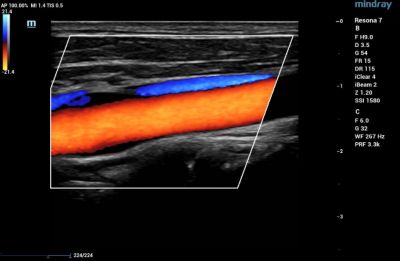

Blood Vessels

Vascular ultrasound is used to evaluate the circulatory system. CDI is used to diagnose and stage acuity of clots in the veins, as well as venous reflux. It is also useful to assess narrowing and blockages within a patient’s arteries.

Color Doppler of Common Carotid Artery

Color Doppler of Posterior Tibial and Peroneal Veins in the calf